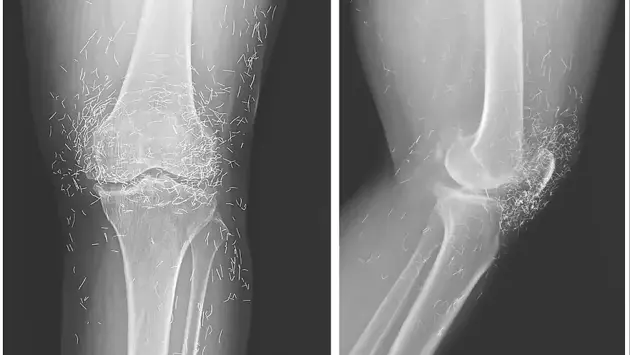

Медики обнаружили золотые нити в колене 65-летней пациентки, которая годами лечила остеоартрит с помощью иглоукалывания. Рентген показал сотни крошечных золотых частиц вокруг коленного сустава, которые попали туда после процедур акупунктуры. Золото должно было дополнительно стимулировать положительную динамику в лечении.

Медики из Медицинского колледжа Сеульского национального университета отметили, что золотые частицы затрудняют чтение рентгеновских снимков и могут мигрировать внутри тела, вызывая повреждения тканей и инфекции.